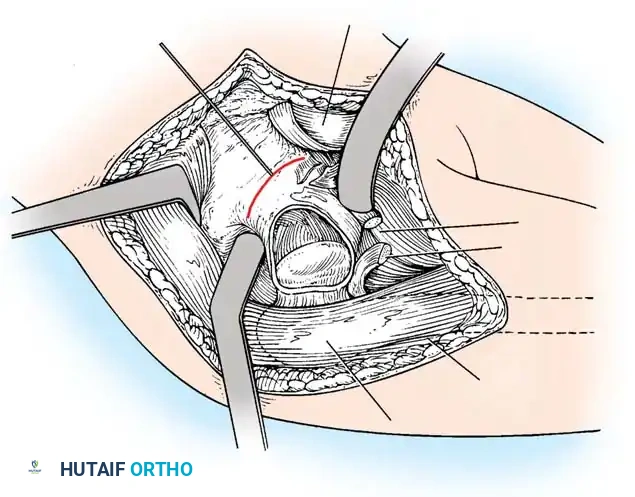

Anterior Approach (Smith-Petersen):

1. Incision: "Bikini" incision below the iliac crest.

2. Interval: Develop the plane between the tensor fasciae latae (superior gluteal nerve) and the sartorius (femoral nerve).

3. Deep Dissection: Detach the rectus femoris from the AIIS. Isolate and release the iliopsoas tendon at the pelvic brim to relieve the hourglass constriction of the capsule.

4. Capsulotomy: A T-shaped or I-shaped capsulotomy is performed parallel to the acetabular margin.

5. Joint Clearance: Excise the ligamentum teres, clear the pulvinar, and incise the transverse acetabular ligament inferiorly. Never excise the limbus, as it is critical for future acetabular growth; radial incisions may be made if it is severely inverted.

6. Capsulorrhaphy: Following concentric reduction, the redundant capsule is advanced superiorly and laterally to stabilize the joint.

Intraoperative view of the anterior approach to the hip, demonstrating capsulotomy and exposure of the dysplastic joint.